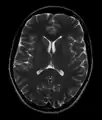

- T2-weighted (T2W) images: CSF is light, but fat (and thus white matter) is darker than with T1. T2-weighted images are useful for visualizing pathology.[26]

Normal axial T2-weighted MR image of the brain